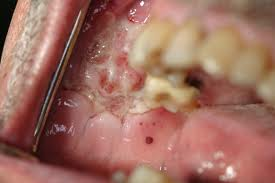

What does oral pemphigoid look like?

Oral pemphigoid typically presents as red or ulcerated patches in the mouth. Blisters may occur but tend to easily break down and leave ulcers. Scarring may be a consequence of oral pemphigoid. The gums are frequently affected, causing them to become red and shiny (desquamative gingivitis), and may be the only manifestation of this condition. The palate (roof of the mouth) is also often involved.